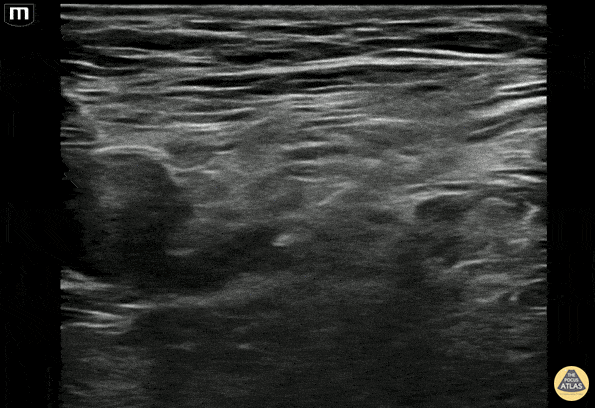

A 70s M w ground level fall pw a left femoral neck fracture. The needle can be seen approaching from the right of the screen (laterally) using an in-plane anteromedial approach. The pulsating left femoral artery is seen on the left of the screen (medial). Adequate hydrodissection is shown with 10cc of normal saline in the fascial space prior to depositing the anesthetic, 30cc of 0.2% ropivacaine. 45 minutes after administration, pain was significantly decreased and the patient was admitted for surgery. Dr. Brigit Noon, PGY-4, Denver Health Emergency Medicine Residency Dr. Matthew Riscinti, Ultrasound Fellowship Director, Denver Health Emergency Medicine Erick Otiniano, MS4, University of California Riverside School of Medicine